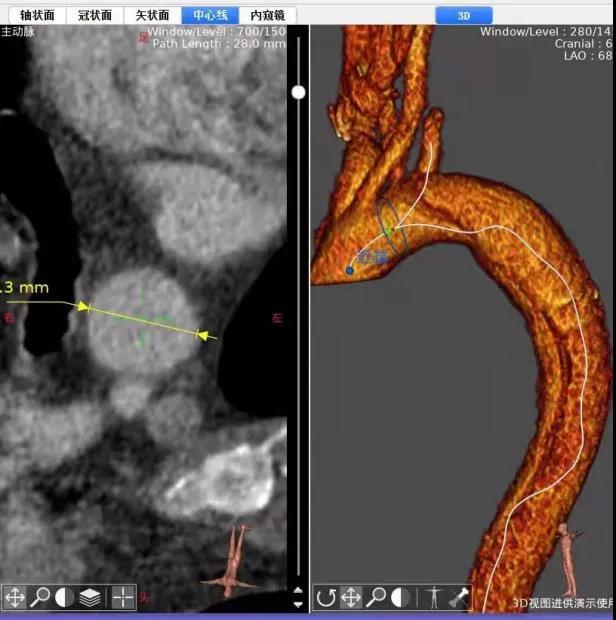

头上多出一根血管——介入科成功救治一例特殊主动脉夹层患者

随着血管介入技术的快速发展,胸主动脉腔内修复术已经成为胸主动脉瘤、主动脉溃疡等疾病的主要治疗方法。